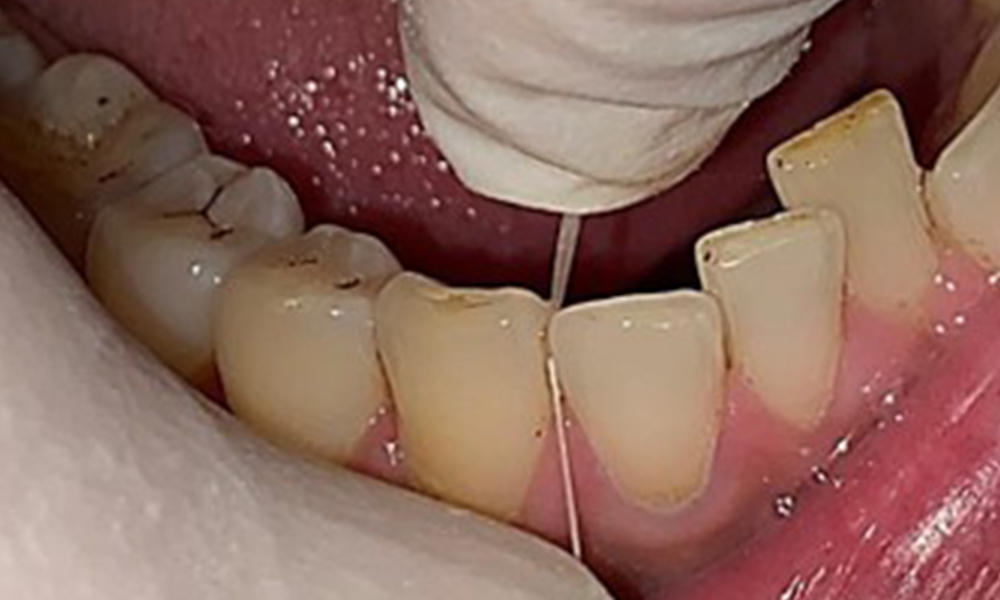

Vue rapprochée des dents

Fig. 5: Vue rapprochée des dents 45 à 47. Les flèches vertes montrent l'attrition dentaire et les érosions des cuspides buccales avec perte partielle d'émail., © Dr R. Krapf

Le patient a une dentition complète avec un total de 28 dents. Il y avait des érosions et des attritions notables. (Fig. 4, Fig. 5). En raison du bruxisme, le patient a porté pendant de nombreuses années une attelle avec une gouttière ajustée la nuit. Les érosions ont été causées par une consommation prolongée de boissons isotoniques. Aucune perte d'os parodontal ou carie active n'a été observée.